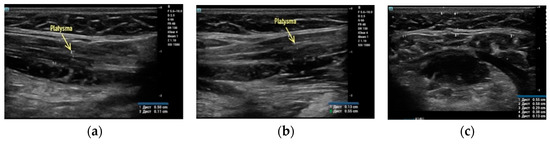

Clinical case #3. During the study, a 46-year-old female patient with a 24 MHz linear transducer of soft tissues of the lower third of the face and neck without pressure, in an upright position, exhibited the absence of the accumulation of adipose tissue along the contour of the lower jaw from two sides (Figure 3a,b) and sagging of a rather thin platysma (diameter 0.36 mm), causing age-related contour deformities (Figure 3c).

B-mode ultrasound examination of the soft tissues of the lower face and submandibular area with a 24 MHz linear transducer. Absence of the accumulation of adipose tissue along the contour of the lower jaw from both sides (a,b), and sagging platysma causes age-related contour deformities (c).

Accordingly, it is correct to direct the efforts of a plastic surgeon to the correction of ptotic platysma in the presented clinical case, which will be sufficient to obtain a good clinical result.